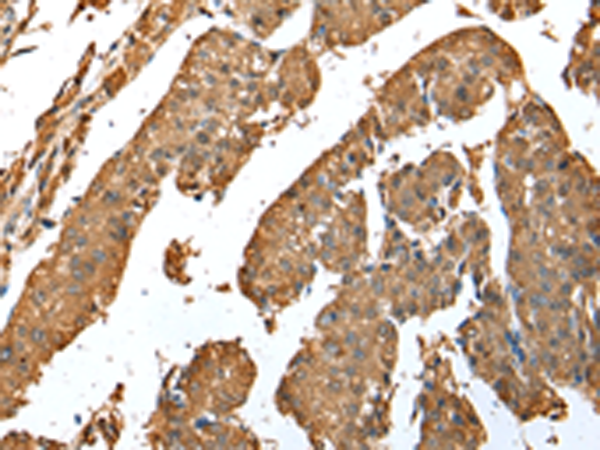

IHC positive control: |

Human liver cancer |

IHC Recommend dilution: |

25-100 |